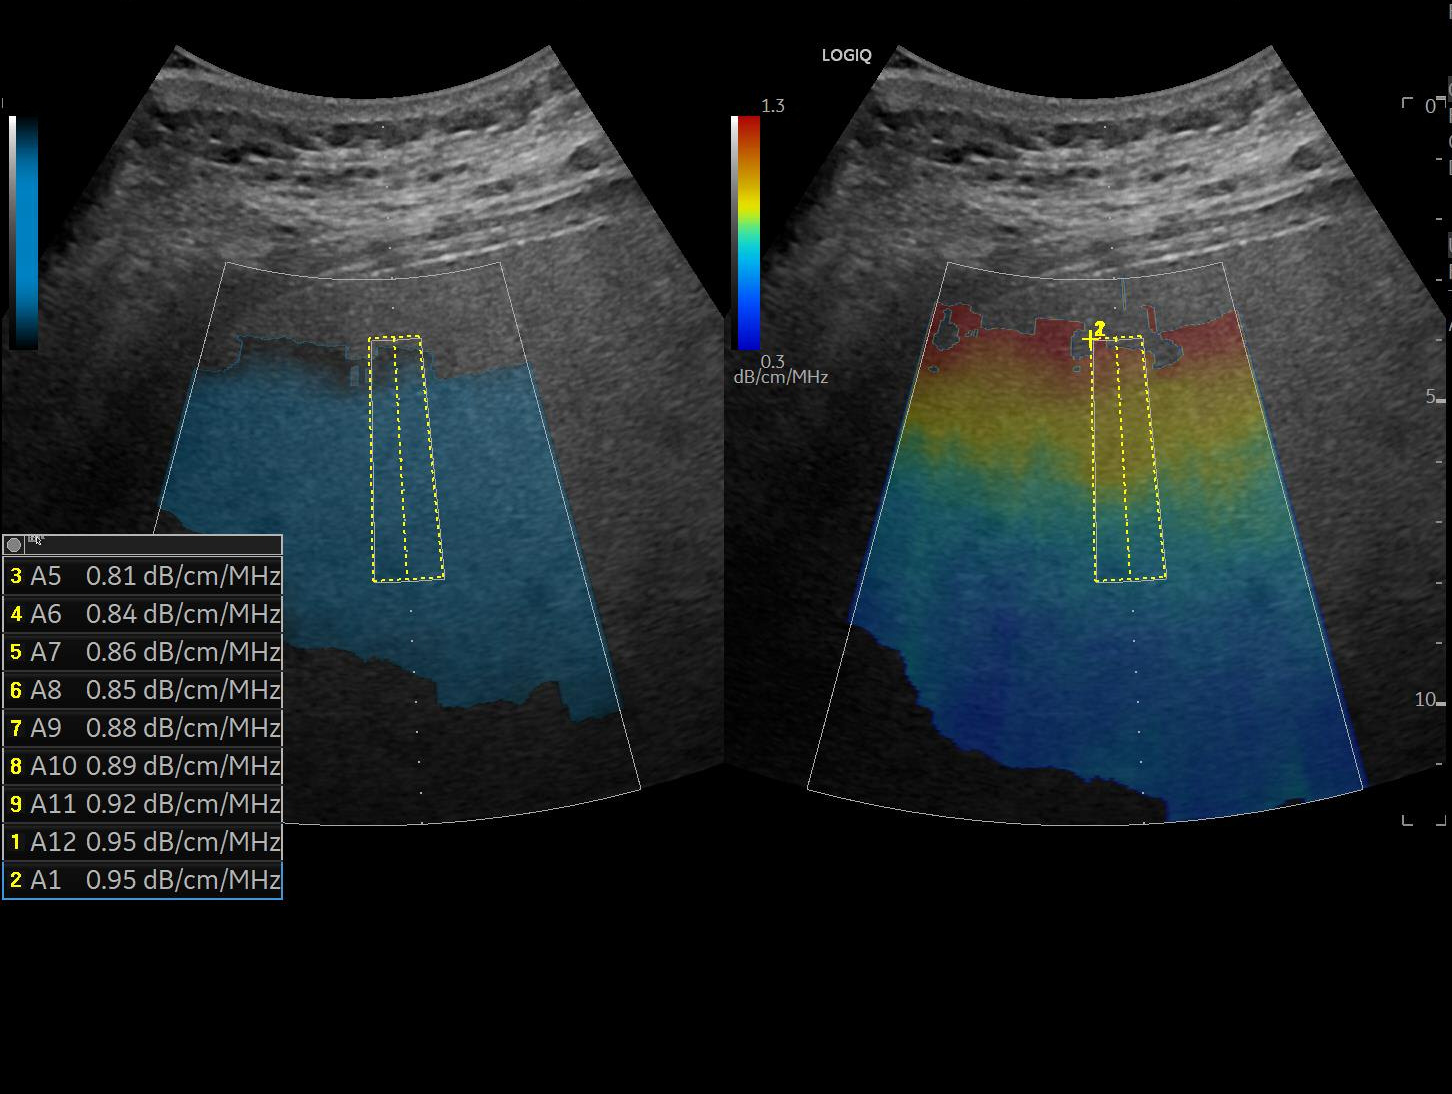

UGAP (Ultrasound-Guided Attenuation Parameter) je nova ultrazvučna tehnika koja omogućava kvantitativno merenje masnoće u jetri, koristeći princip slabljenja ultrazvučnog talasa dok prolazi kroz jetreno tkivo. Ova metoda koristi napredne algoritme koji automatski prepoznaju optimalno mesto za merenje i eliminišu smetnje poput krvnih sudova ili rebara, čime se obezbeđuje tačniji rezultat.

Kada ultrazvučni talas prolazi kroz jetru, on gubi energiju zbog interakcije sa tkivom. U normalnoj jetri, ovaj gubitak je minimalan, ali u jetri sa viškom masnoće, ultrazvučni signal se značajno slabi. UGAP meri koliko se talas oslabi (izraženo u decibelima po centimetru po megahercu - dB/cm/MHz) i na osnovu toga određuje stepen masne jetre. Prednost UGAP metode u odnosu na klasični ultrazvuk je u tome što ne zavisi od iskustva lekara, podešavanja aparata ili drugih subjektivnih faktora – ona pruža objektivan brojčani rezultat koji se može uporediti sa prethodnim merenjima.